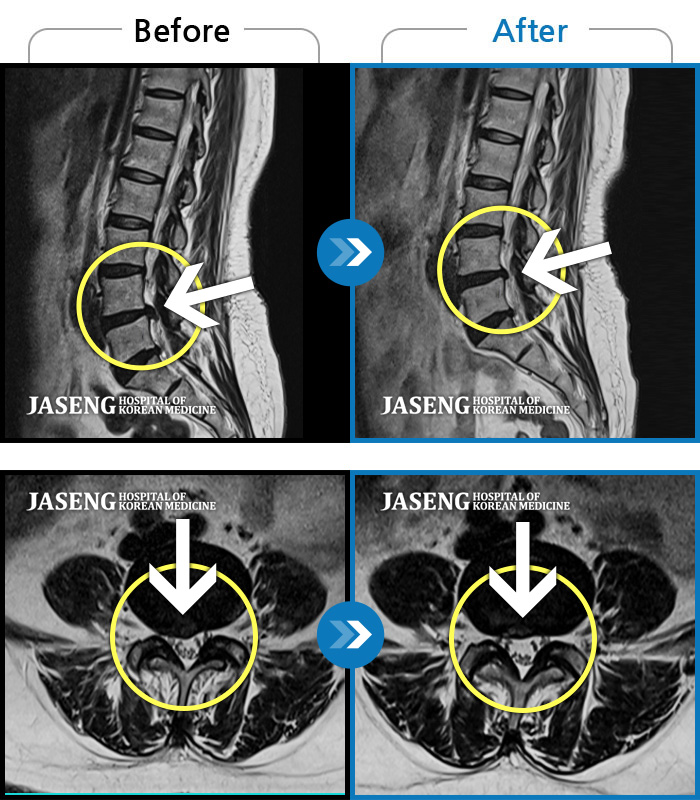

허리디스크

광주 · 김동은 원장

양측 허리부터 양측 골반까지 당기는 통증, 양측 하지 후면으로 이어지는 통증

촬영시기

2022.09.05 ~ 2024.05.06

2024.05.24